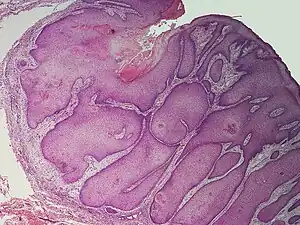

Pilar sheath acanthoma

A pilar sheath acanthoma is a cutaneous condition most often found on the face, particularly above the upper lip in adults.[1]: 675